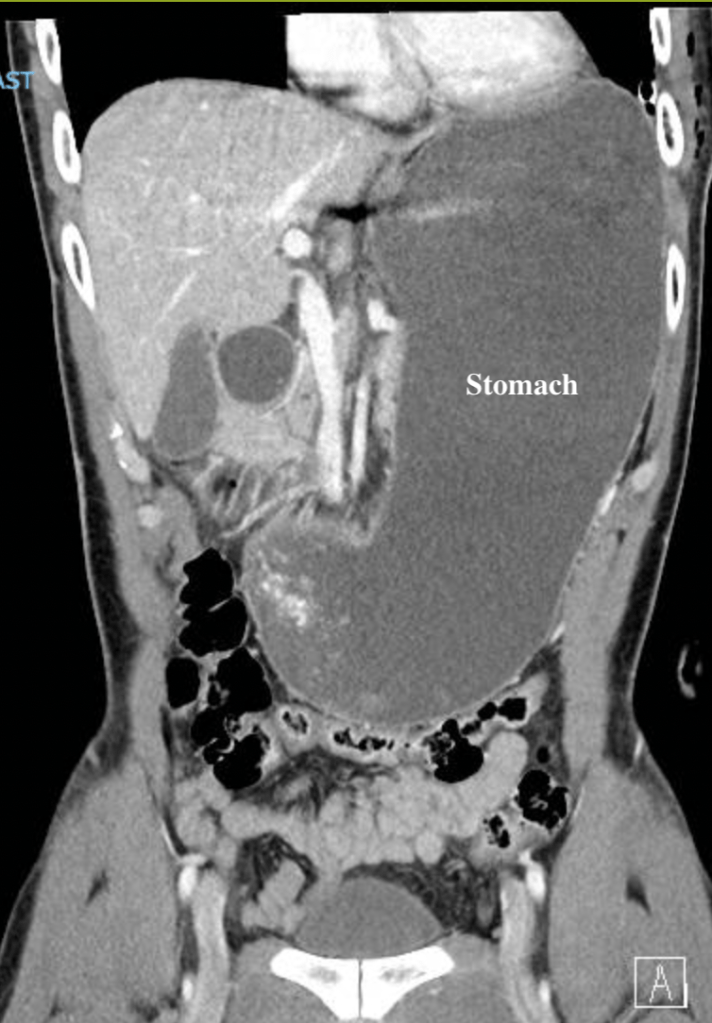

4. Since my last post, I have had 4 scans (all clear!). My oncologist and I started to have the talk – when should we start increasing time between scans? It’s crazy to think that since diagnosis, I have had 80+ scans (am I mutant yet?) and over 40 office visits with my oncology team. I remember in one of the first visits – when I started on the quarterly cadence – Dr. Hall said “I hope you live long enough so I can see you less often”. In case you are unfamiliar, these various scans (CT, MRI, PET) are all fantastic ways to monitor for progression; however, they emit a ton of radiation that accumulates over time and radiation is a known cause of cancer. As a doctor, I can certainly understand wanting to space out scans more because the act of monitoring cancer can actually cause new cancer, but as a patient the scans give me peace of mind that there is nothing to worry about (at least for 3 months at a time).